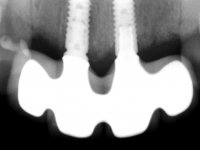

Foram feitas as extrações das raízes dos dentes 2.1 e 2.2 porque estavam a incomodar. Após 3 meses de cicatrização fez-se o exame imagiológico e estudo implantar para colocação do implante no local do 2.1.Foi colocado um implante de 4.1mm de diâmetro por 10mm de altura, colocado ao nível ósseo. Passados 2 meses após a cirurgia implantar, foi feita a segunda cirurgia para colocação de um parafuso de cicatrização. Foi feita a impressão ao implante com técnica de moldeira aberta com silicone de dupla viscosidade um mês após. No laboratório foi confecionada uma infraestrutura metálica para uma ponte de 2 elementos aparafusada ao implante. Esta infraestrutura apresentava 2 apoios palatinos para ajudar a estabilizar os dentes 1.1 e 2.3 a recuperar do traumatismo. Recuperados os dentes, os apoios poderiam ser retirados. Esta peça apresentava uma conexão interna ao implante com sistema anti-rotacional. A prova da infraestrutura foi feita em boca sendo o seu correto ajuste verificado com controle imagiológico. No revestimento da infraestrutura foi utilizada cerâmica de tonalidade coronária e gengival. Depois de verificada em boca e aprovada pelo paciente a ponte foi apertada definitivamente e o orifício de acesso obturado.

6 meses após a colocação da ponte, o paciente sofre um novo traumatismo comprometendo a viabilidade dos dentes 1.2 e 1.1. Foi realizada uma prótese removível acrílica para reabilitar provisoriamente o paciente enquanto foram extraídos os dentes 1.2 e 1.1 e foi colocado o implante no local do dente 1.1. Passados 3 meses foi realizada uma impressão ao implante colocado no 1.1 e simultaneamente foi feito um arrasto da ponte dos dentes 2.1 e 2.2. Para esse efeito no implante 2.1 foi utilizado um parafuso de uma peça de transferência. Dessa forma conseguiu-se impressionar corretamente a arquitetura gengival do sector antero-superior. O objetivo era simultaneamente impressionar corretamente esta zona e aproveitar a estrutura metálica desta ponte para confecionar a nova ponte de 4 elementos. Foi colocado um parafuso de cicatrização no implante 2.1 e foram acrescentados os dentes 2.1 e 2.2 na prótese removível. Com perícia laboratorial foi criada uma nova infraestrutura metálica de 4 elementos assente nos implantes 1.1 e 2.1 e com os elementos pônticos suspensos 1.2 e 2.2. No implante 2.1 manteve-se a conexão interna ao implante no implante 1.1 optou-se por uma peça intermédia facilitando a inserção da infraestrutura. A nova infraestrutura foi verificada em boca. Como pode ter havido alguma alteração da arquitetura gengival com a remoção da ponte e colocação do parafuso de cicatrização no 2.1, foi feita uma chave de silicone para permitir uma impressão de arrasto da infraestrutura metálica. Uma nova gengiva artificial foi realizada no modelo de trabalho de acordo com esta impressão de arrasto. Foi colocada cerâmica de tonalidade coronária e gengival. A peça protética foi aparafusada lentamente em boca para permitir uma adaptação dos tecidos moles. Após o correto assentamento e verificação imagiológica a ponte foi definitivamente apertada em boca e os orifícios de acesso obturados. Independentemente dos infortúnios que o paciente teve, pude ter a satisfação de o ver contente com esta reabilitação.